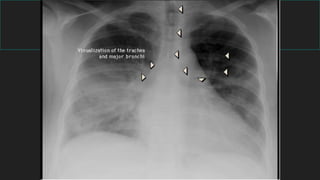

5- Hilios y vía aérea

Tráquea

- Región central mediastino superior

- Indentación borde aórtico (frente)

Bifurcación traqueal

- Ángulo de bifurcación: 55º - 70º

- Bronquio derecho tiene una

dirección más vertical que el izquierdo